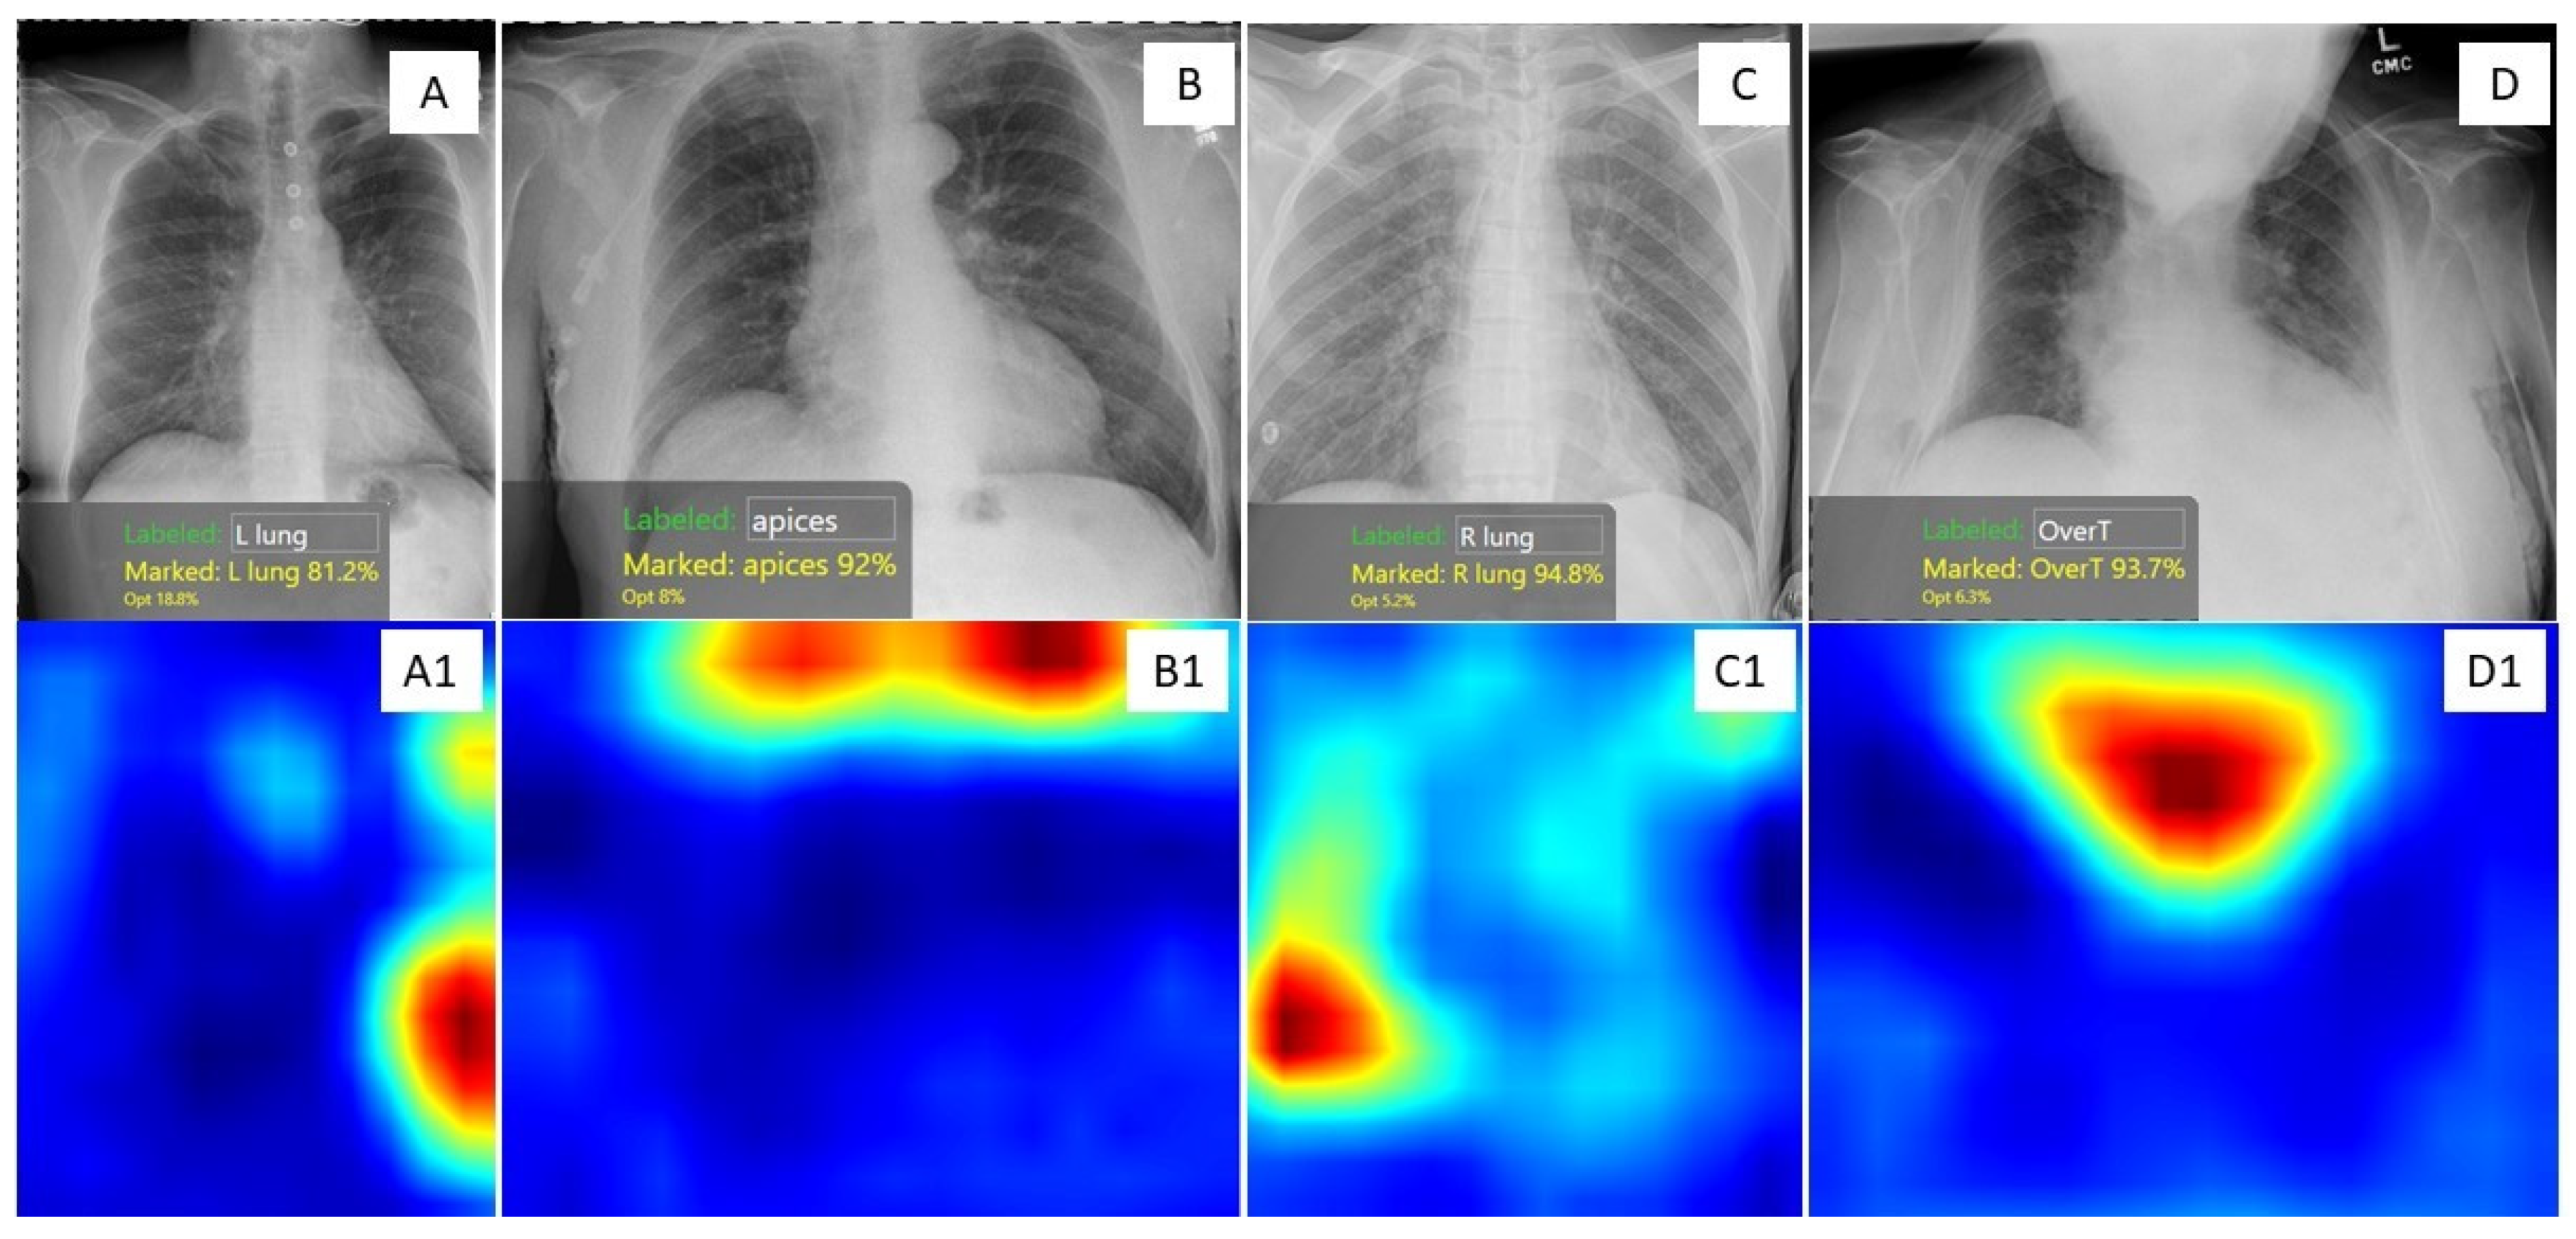

- Dasegowda, G.; Bizzo, B.; Gupta, R.V.; Kaviani, P.; Ebrahimian, S.; Ricciardelli, D.; Abedi-Tari, F.; Neumark, N.; Digumarthy, S.R.; Kalra, M.K.; et al. Successful creation of clinical AI without data scientists or software developers: Radiologist-trained AI model for identifying suboptimal chest-radiographs. Res. Sq. 2022. [Google Scholar] [CrossRef]